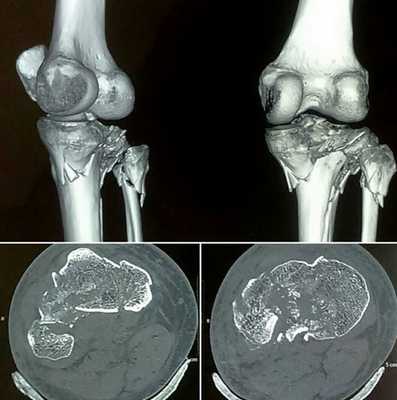

КТ суставов что показывает

Компьютерная томография является современным видом аппаратной диагностики. Метод позволяет визуализировать внутренние структуры без инвазивных манипуляций. С помощью КТ суставов определяют патологии опорно-двигательной системы различной этиологии и генеза.

Изменения головки большеберцовой кости на томограмме

Компьютерную диагностику осуществляют с помощью рентгеновского излучения. Ионизирующие потоки проходят сквозь тело человека. Пропускная способность разных участков зависит от строения анатомических структур. Кости и хрящи обладают высокой рентгеноконтрастностью, сканирование рыхлых суставных элементов менее результативно.

Для большей информативности при обследовании мягкотканных структур применяют контрастную компьютерную томографию. В кровеносное русло вводят «окрашивающий» препарат на основе йода. Вещество обладает высокой поглощающей способностью в отношении рентгена, позволяет визуализировать сосудистую сеть и оценить строение всех морфологических элементов сочленения.

Что покажет КТ суставов и костей?

В результате томографии получают монохромные изображения тонких срезов изучаемой зоны. В отличие от линейной рентгенографии, КТ костей и суставов позволяет рассмотреть сочленение в трех взаимно перпендикулярных проекциях. На томограммах отсутствуют тени и дефекты от расположенных рядом анатомических образований.

Изображения КТ дают информацию о плотности исследуемого вещества. Светлые пятна на фото соответствуют твердым структурам, затемнения - мягкотканным участкам.

Компьютерная томография колена

В диагностике заболеваний суставов КТ позволяет выявить:

переломы костных суставных поверхностей;

Остеосаркома бедренной кости на снимке коленного сустава

Для уточнения локализации и размеров патологического очага врач может использовать пространственное изображение области интереса . На основании фотографий, полученных в результате сканирования, реконструируют 3D-модель рассматриваемой зоны. Трехмерная визуализация позволяет оценить характер взаимодействия здоровых и пораженных тканей.

КТ колена

С помощью компьютерной томографии визуализируют нарушения связочного аппарата, костных суставных поверхностей, гиалинового хряща, синовиальной оболочки и капсулы сочленения. Ограничение подвижности и боль возникают чаще при травмах, воспалительных и дегенеративных патологиях.

КТ коленного сустава позволяет диагностировать хондромаляции (разрушение хряща), повреждения менисков, разрывы крестообразных связок. В результате контрастной процедуры выявляют онкологические процессы, заболевания сосудов, липоартрит и пр.